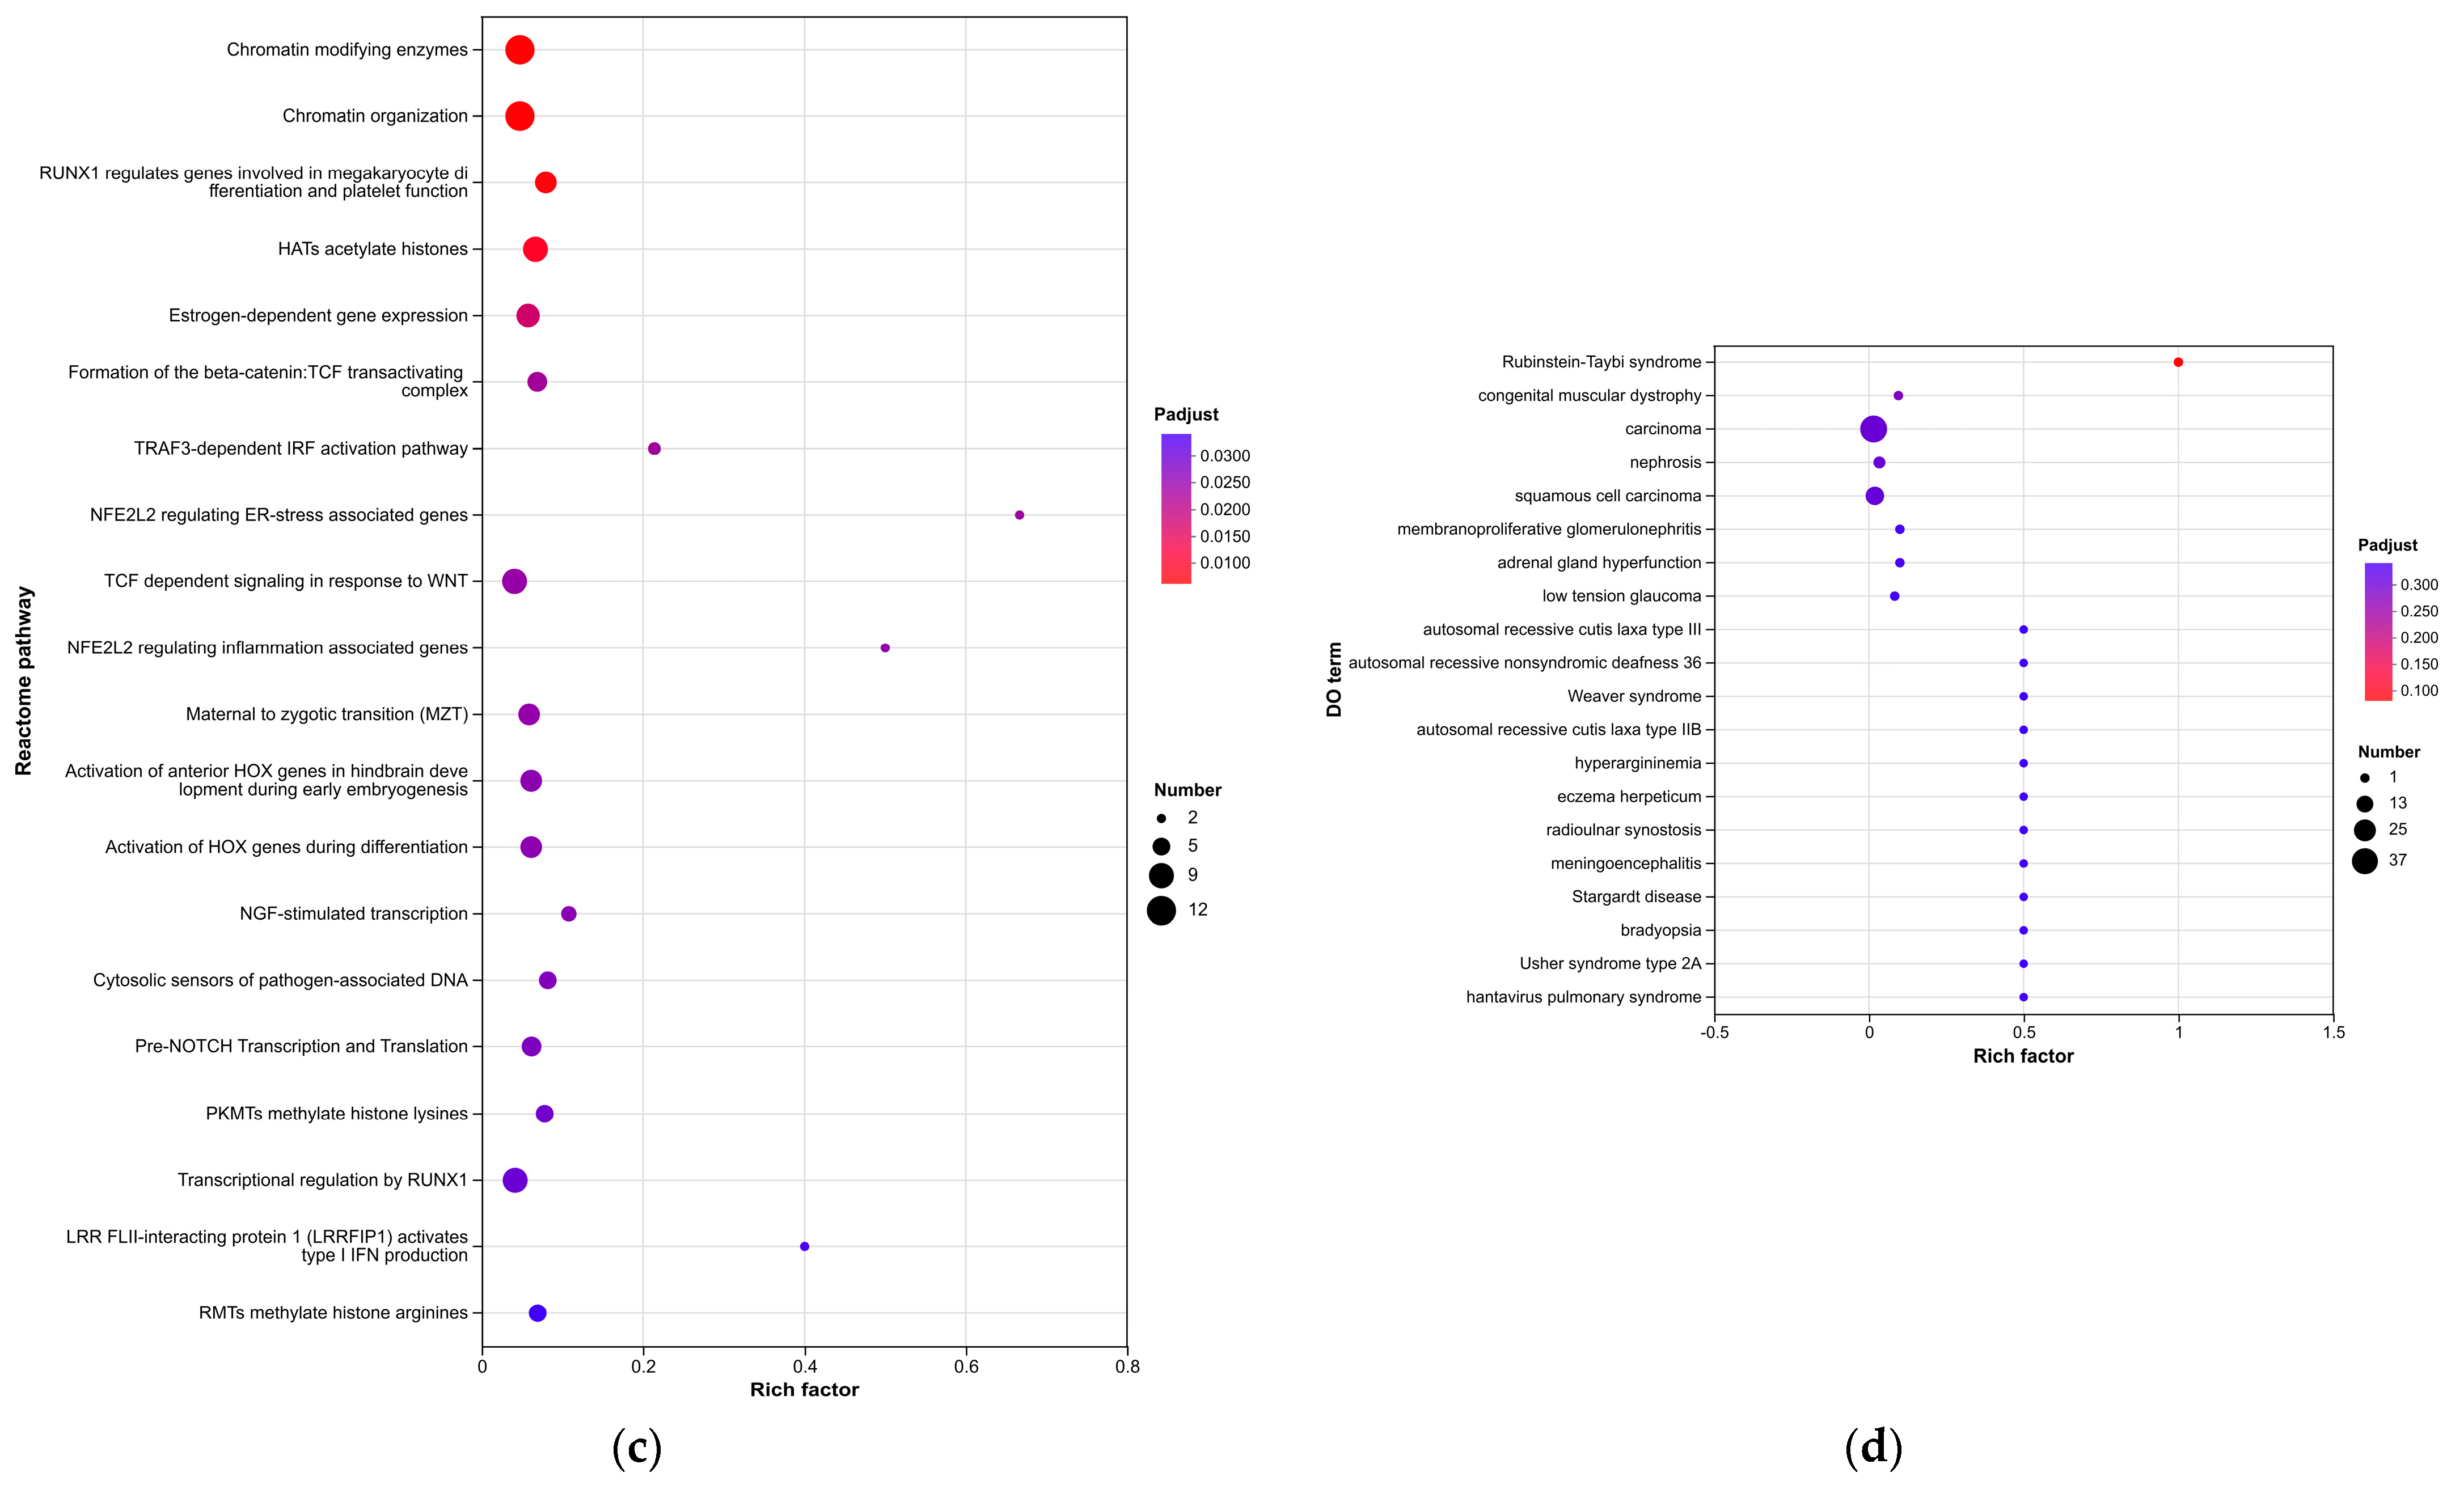

Enrichment analyses, grouped by functional categories (

Table 3), revealed a predominance of RNA processing and immune response pathways consistent with

C. acnes-induced inflammation. These analyses further identified the C-type lectin receptor (CLR) signaling pathway as a key mediator of

C. acnes IA

1–induced inflammation. CLRs, expressed on keratinocytes and immune cells, recognize bacterial glycans, activating NF-κB and MAPK pathways to drive cytokine production [

25]. Our KEGG results, which also enriched NF-κB signaling, suggest a synergistic mechanism where

C. acnes IA

1 exploits CLR-mediated recognition to amplify inflammatory cascades, contributing to the chronicity of acne lesions [

26]. Additionally, enrichment of interferon-mediated signaling and Notch signaling indicates broader immune modulation, with interferons enhancing antiviral-like responses against bacterial PAMPs and Notch regulating epidermal differentiation [

27]. Reactome and Disease Ontology (DO) analyses further linked DEGs to chromatin modification and dermatological conditions, reinforcing acne’s inflammatory nature akin to psoriasis or eczema [

28].